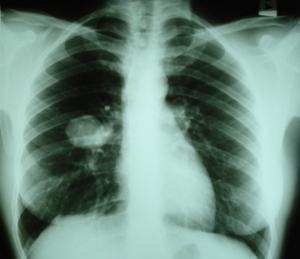

Εικόνα 1

Οπισθιοπροσθία ακτινογραφία του θώρακος. Διακρίνεται ευμεγέθης σκίαση στο μέσο πνευμονικό πεδίο του δεξιού πνεύμονος, με ομαλά όρια.